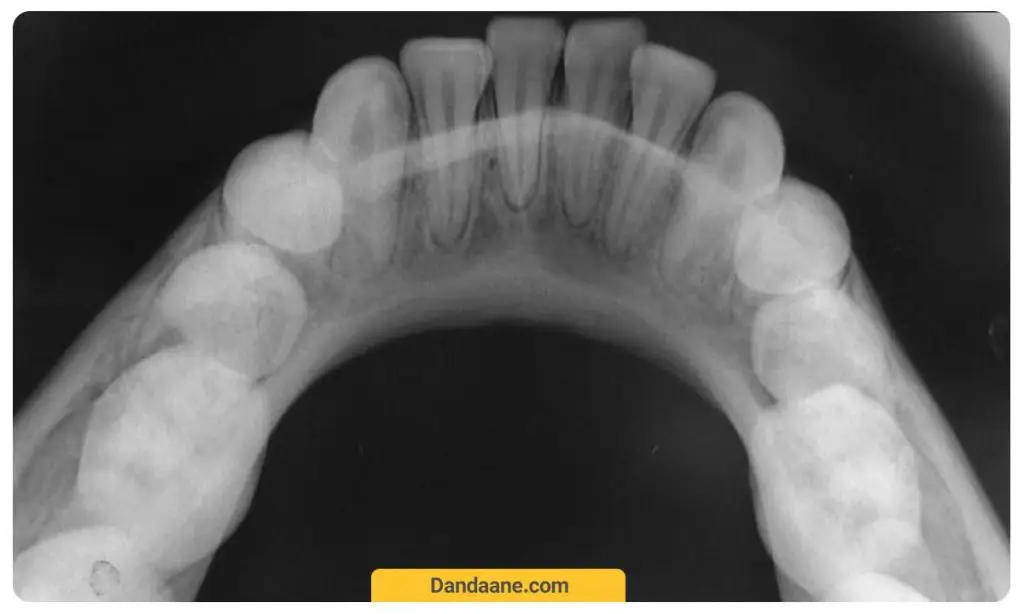

رادیوگرافی اکلوزال یا (Occlusal)

عکس دندان اکلوزال تصویری از نمای اکلوزال یا سطح جونده دندان است. در این رادیوگرافی که معمولا بزرگ تر از سایر عکس های دندانی دیگر است برای ارزیابی نحوه رشد دندان های شیری و دائمی کودک استفاده می شود. هر رادیوگرافی اکلوزال دندان تقریبا تمام طاق فک بالا و یا پائین را نشان می دهد.